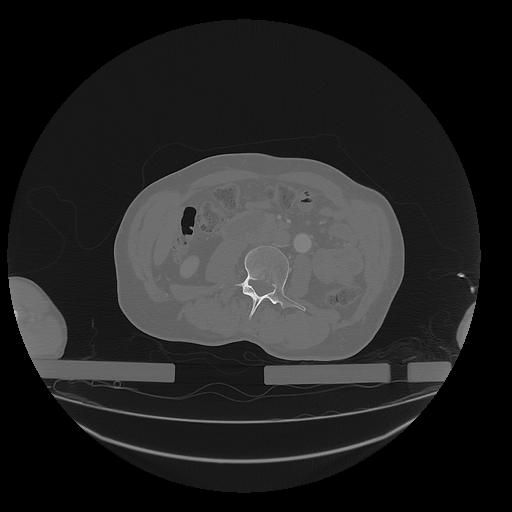

31 PULMON,CE,Vol,1.0,PULMON,,